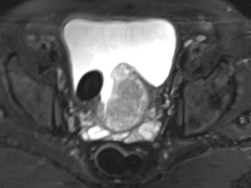

68岁的张大爷(化名)十多年来一直排尿不顺畅,夜尿频繁,逐年加重。两年前,排尿时开始感到下腹部疼痛。近期出现了排尿中断的情况,有时还伴随尿痛。在家人的陪伴下,张大爷来到我院泌尿外科就诊。

经检查,患者前列腺体积大小达到200ml,与蟠桃相当,而正常前列腺仅20ml,且合并巨大膀胱结石,这正是导致其症状加重的主要原因。